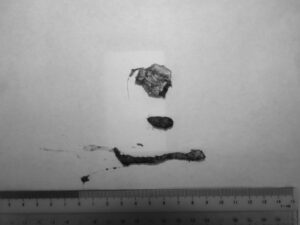

吐き気が続いて、元気・食欲がないワンちゃんが来院されました。超音波検査で異物による小腸閉塞が疑われましたので緊急手術となりました。腸を切開し異物を摘出し、無事手術は終了、元気に退院していきました。よかったね。